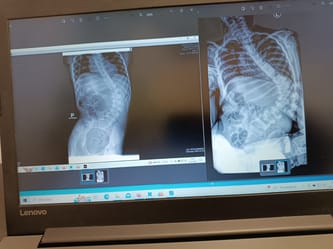

Dziewczynka przeszła wiele zabiegów i operacji, między innymi wszczepienie zastawki komorowo-otrzewnej. Oliwka zmaga się z wieloma schorzeniami. Zdiagnozowano u niej Mózgowe Porażenie Dziecięce. Przeszła też terapię komórkami macierzystymi, za którą rodzice zapłacili 100 tysięcy złotych. Efekt był zauważalny, jednak nie na długo. Oliwka potrzebuje stałej rehabilitacji oraz szeregu innych terapii, których łączny miesięczny koszt przekracza 10 tysięcy złotych. Nie to jest jednak najgorsze. W związku z chorobami towarzyszącymi dziewczynce od urodzenia, doszło do ekstremalnego skrzywienia jej kręgosłupa. Szczerze, nikt z nas nie widział nigdy takiego zdjęcia RTG. Skolioza jest tak głęboka, że istnieje realne zagrożenie uszkodzeniem ośrodka odpowiedzialnego za oddychania. Kiedy tak się stanie, Oliwka będzie niewydolna oddechowo, a to całkowicie przekreśli szansę na dalszą rehabilitację. Czeka ją wiele skomplikowanych operacji oraz długotrwała i męcząca rehabilitacja. Koszty również nie są małe.